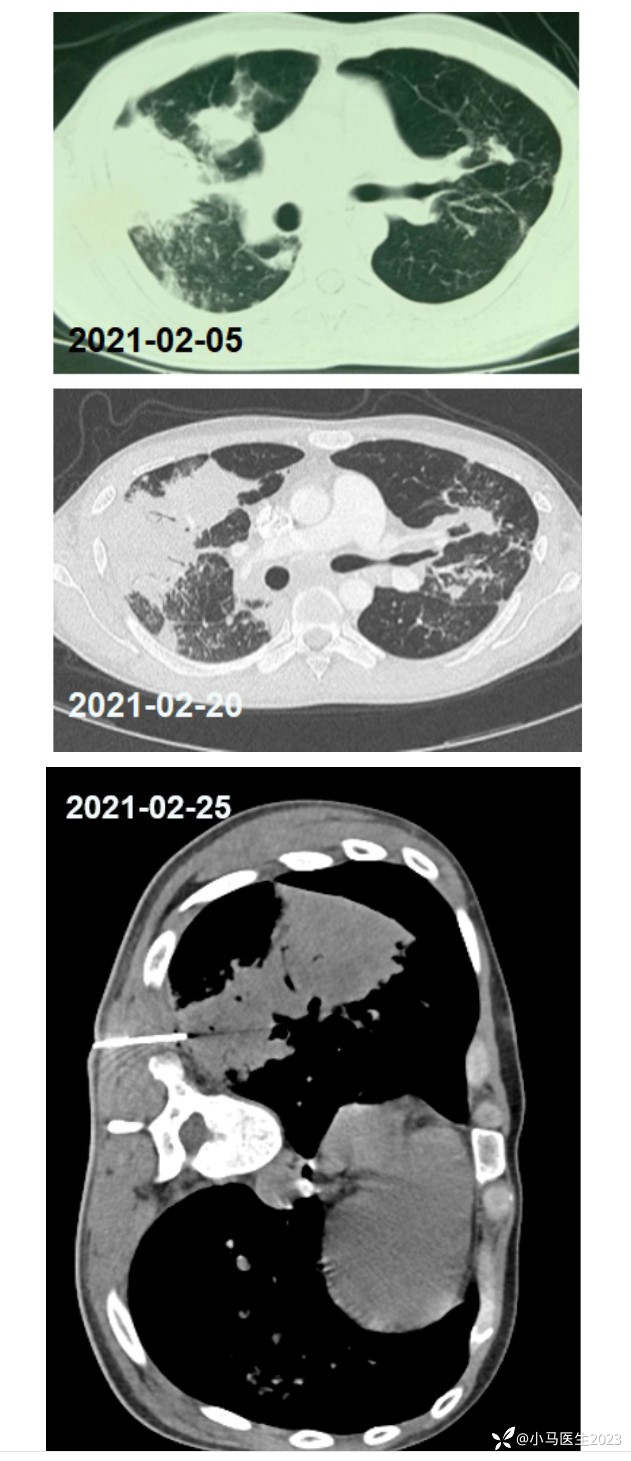

停用激素后病灶增多

患者要求经验性治疗,予甲泼尼龙40mg qd×7天,03-15复查

胸部CT无明显变化,予口服甲泼尼龙40mg带药出院

第四次入院 03-29

03-29复查胸部CT进展

胸部CT对比